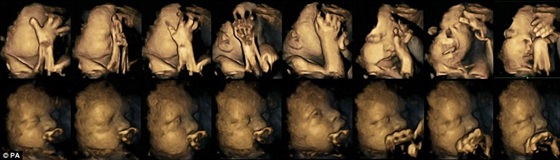

السوسنة - أجرى الباحثون بجامعة "جيمس كوك" ببريطانيا، فحصا بالموجات فوق الصوتية للأمهات المدخنات لرصد تأثير التدخين على الأجنة في الأرحام.

حسب ما نشرته صحيفة "ديلى ميل" البريطانية، أجريت الدراسة على 20 امرأة مدخنة تتراوح مدة حملهن بين "24، 28، 34، 36" أسبوعا منهن 4 يقمن بتدخين 14 سيجارة في اليوم.

وأوضحت الأشعة أن الأطفال الذين تدخن أمهاتهم يضعن أيديهم على وجوههم وأفواههم بصورة أكثر مما تفعله الأجنة التي لا تتعرض لدخان السجائر.

يذكر أيضا أن التدخين يؤدى إلى مشاكل في الجهاز التنفسى للطفل قد تؤدى للموت، وكذلك تأخر في نمو واكتمال الجهاز العصبى، أيضا خطورة التعرض للولادة المبكرة، كما يأمل الباحثون أن تجعل تلك الصور المؤلمة المدخنات يفكرن في الإقلاع عن التدخين.